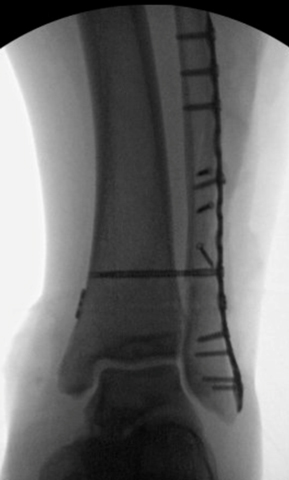

TOTAL ANKLE REPLACEMENT :: ORIF CALCANEUS :: ORIF ANKLE FRACTURE DISLOCATION :: COMPLEX BUNION AND LESSER TOE CORRECTION :: TALUS FRACTURE -1 :: TALUS FRACTURE -2 :: LISFRANC REPAIR :: COMPLEX TRIPLE ARTHRODESIS 1 :: COMPLEX TRIPLE ARTHRODESIS 2 :: MINIMALLY INVASIVE BUNION REPAIR 1 :: MINIMALLY INVASIVE BUNION REPAIR 2 :: ARTHROSCOPIC CARTILAGE REPAIR :: TENEX SPUR DEBRIDEMENT :: Haglunds Debridement and Achilles Repair